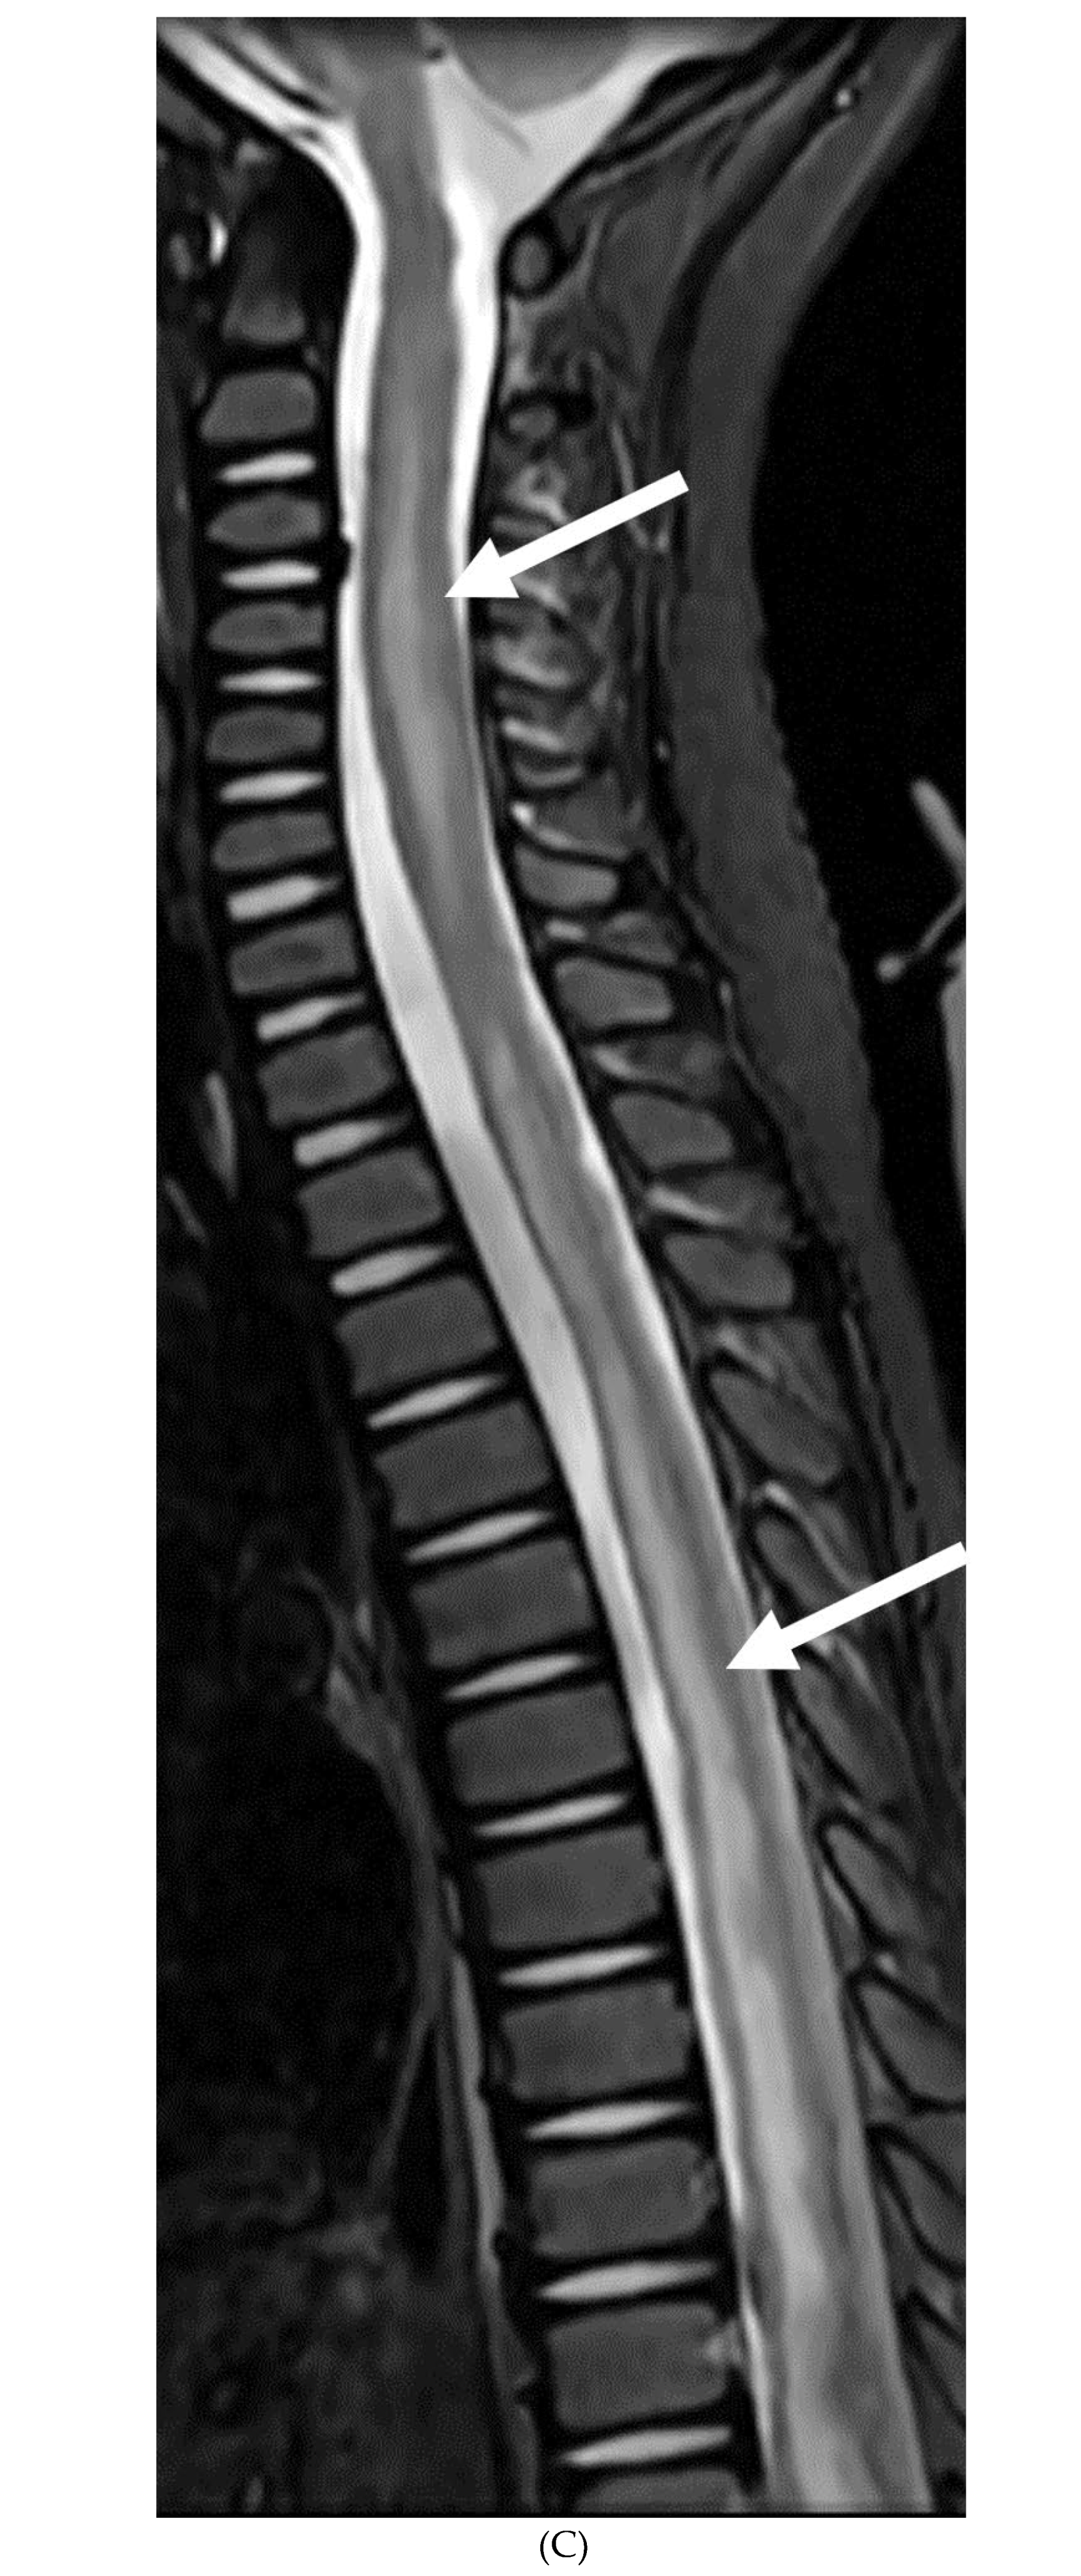

GUILLAIN BARRE SYNDROME

- Alkan O, Yildirim T, Tokmak N, Tan M. Spinal MRI findings of guillain-barré syndrome. J Radiol Case Rep. 2009;3(3):25-8. Epub 2009 Mar 1. PMID: 22470650; PMCID: PMC3303301. [CrossRef]

- Byun WM, Park WK, Park BH, Ahn SH, Hwang MS, Chang JC. Guillain-Barré syndrome: MR imaging findings of the spine in eight patients. Radiology. 1998 Jul;208(1):137-41. PMID: 9646804. [CrossRef]